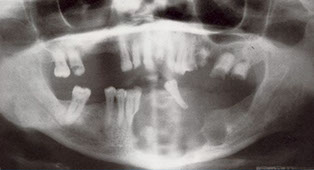

2nd MCC of odontogenic cyst (~1/5 epithelium-lined jaw cysts), and the MCC of developmental odontogenic cyst; usually in young adults and teens

- assoc c crown of an unerupted (or partially erupted) tooth, usually the mandibular third molars (wisdom teeth)

- may be found on radiographs taken for delayed tooth rupture; usually painless, can be painful if infected; can be large enough to displace involved teeth and cause resorption of adjacent teeth

Imaging: usually a well-defined, unilocular radiolucency on X-ray c sclerotic rim (can look the same as KCOT and ameloblastoma)

Micro: cyst cavity lined by stratified squamous epithelial cells from reduced enamel epithelium of the tooth forming organ

- has no rete ridges, flat interface, lining epithelium 2-4 layers of cuboidal epithelium

DDx: Cystic ameloblastoma (usually has reverse polarization of nuclei [away from BM]); KCOT (has hyperchromatic basal palisading of cuboidal / columnar cells, and wavy surface parakeratosis)

Px: excellent, almost never recur c complete enucleation